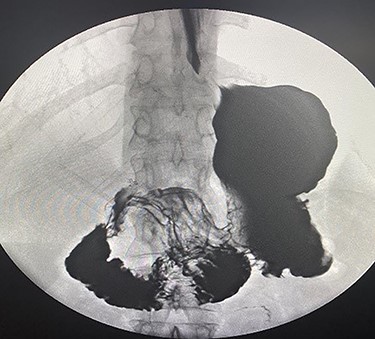

The patient taken to the operating room for diagnostic laparoscopy and proceed, after insufflating the abdomen the whole abdomen examined and showed proximal dilatation of small intestine with collapse of distal part of jejunum, the ileocecal junction identified and the small bowel examined proximally till the obstruction identified, which is fibrous band originating from the stomach to the proximal part of jejunum (Fig. 3), examination of this band showed that this band is caused by suture penetrating the stomach wall, which is going with the previous history of the endoscopic gastroplasty, reduction of the internal hernia done by releasing of the fibrous band, the herniated segment was healthy (Fig. 4).

Fibrous band originating from the stomach to the proximal part of jejunum.